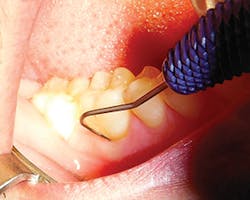

To evaluate for furcation involvement, select a furcation probe (e.g., Nabers or ACE probe). The ACE probe is the next generation of probes, a straight furcation probe that is both flexible and more accurate with a newly designed periodontal probe on the other end that is designed for patient comfort (see Figure 5).

Insert the probe into the furcation locations, as shown on Figure 6. Measure and record any tooth numbers with a furcation grade (I, II, III, or IV). Refer to Glickman guidelines, and see Table 2. Focus on furcations grade I-II for the optimal time and grade III with at least one wall for regenerative treatment, such as guided bone rengeration (GBR) (see Figure 7). If the furcation progresses to a grade IV, the studies now recommend extraction and/or implant placement due to the oral-systemic risk to the patient.6,9

Report to the dentist any furcations with grade II-III and at least one wall present for possible GBR treatment.